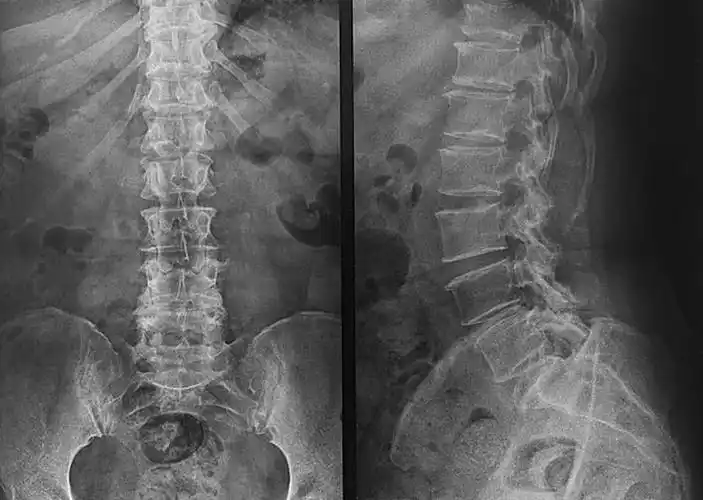

大家看看孩子的骨盆和脊柱有没有问题

x光,脊椎

x光,骨盆,脊椎_高清图片_全景视觉

ct腰椎或l-s脊柱三维渲染图像前,后,侧位视图.